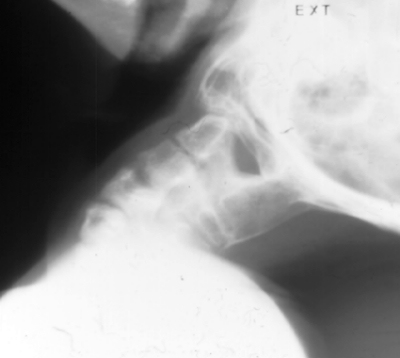

The cervical spine is commonly involved. Often there are multiple vertebral fusions, C2 - C3 fusion, odontoid abnormalities, odontoid absence, and ball and socket occiput-atlanto joint with or without instability.